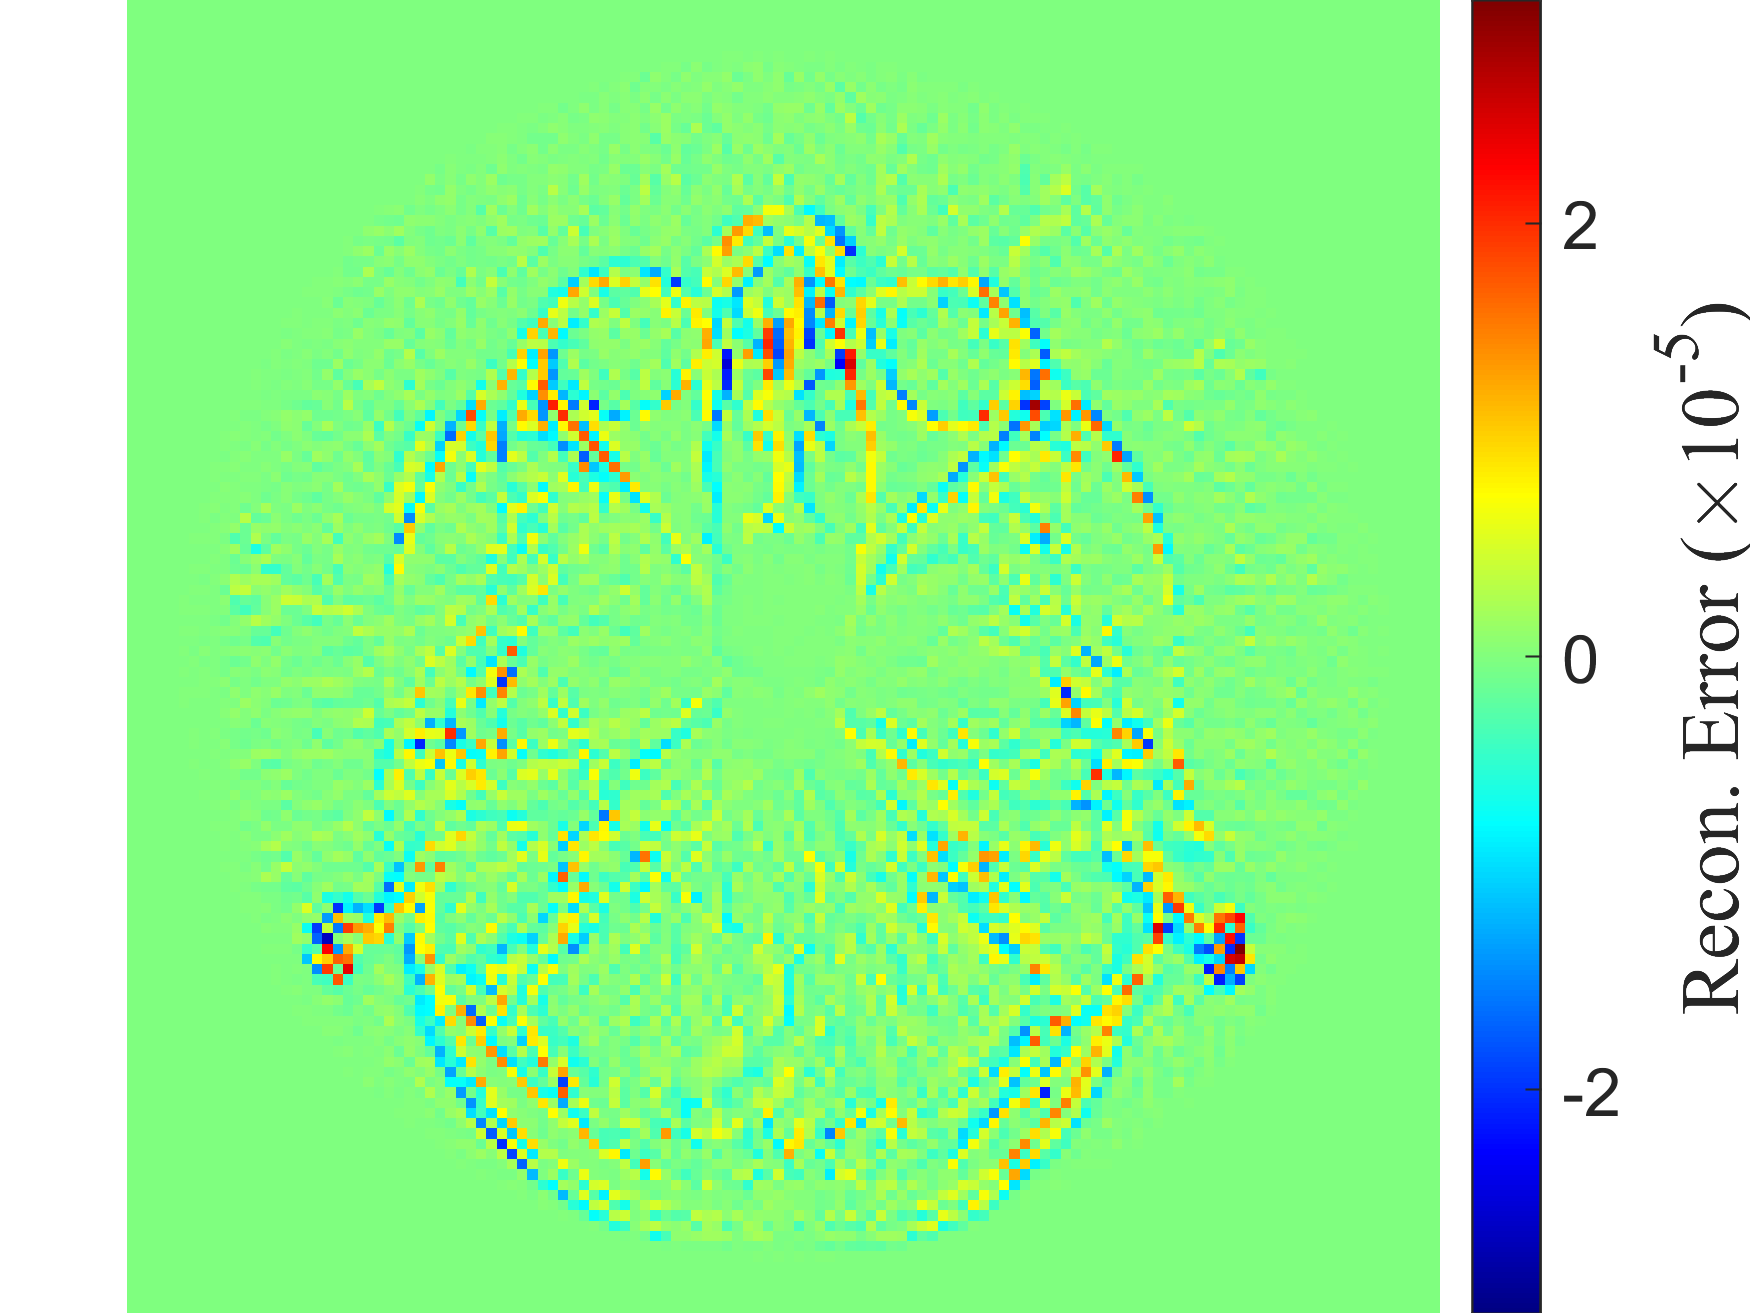

Refer to caption

(h) DDM

(i) Original density profile

(j) kk-NN

Figure I.3: Representative original and reconstructed density profiles for the Hughes 2D pedestrian model dataset (M=200×50M=200\times 50). Left column panels show the original density profile, while panels 3(b), 3(d), 3(f), 3(h) and 3(j) show its reconstructions, obtained with the five decoders: RANDSMAP-RFF with P=NP=N, RANDSMAP-MS-RFF with P=NP=N, RANDSMAP-Sig with P=NP=N, DDM and kk-NN, respectively. For the RANDSMAP decoders, the displayed configuration is the one achieving the lowest training error among all variants of that type (see full comparison in Fig. 4(a)).